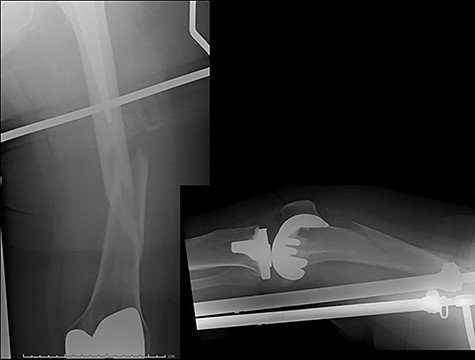

Case 4 (Figs 8–10): once again, screw placement too close to the fracture site has resulted in internal plate stresses exceeding its load-bearing capacity.

Inter-fragmentary screws have been utilized here. This lady may have benefited from placing an anterior bridging plate at the time of her original procedure if it was not possible to avoid this screw configuration.